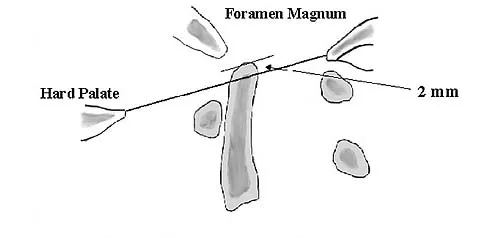

Question 65

A 55-year-old woman with a history of untreated idiopathic scoliosis has had neurogenic claudication for the past several months. MRI reveals spinal stenosis at L2-L3, L3-L4, and L4-L5. Radiographs show a 45-degree lumbar curve from T10 to L4, with a degenerative spondylolisthesis at L4-L5. Laminectomy at the stenotic levels and stabilization of the deformity are planned. Which of the following is NOT considered an absolute indication for extending the fusion to the sacrum, rather than stopping at L5?